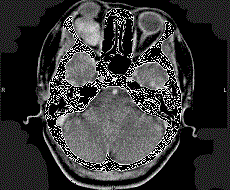

问题 41岁女性,右眼胀痛、眼球外突3月余,体检,发现低头时右侧眼球外突加重,CT检查如图所示,请选择最可能诊断 ( )

选项 A、右侧眶内神经鞘瘤 B、右侧眶内皮样囊肿 C、右侧眶内炎性假瘤 D、眼型格氏病 E、右侧眶内血管瘤

答案 E